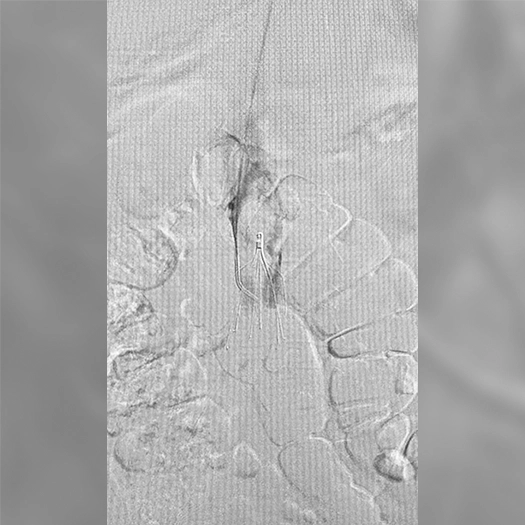

Venous Cases

Images used with permission and provided for illustrative purposes only. Procedural techniques and decisions based on physician’s medical judgment. Individual results may vary. Consents on file at Penumbra, Inc.